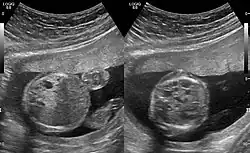

CPAMs are often identified during routine prenatal ultrasonography. Identifying characteristics on the sonogram include: an echogenic (bright) mass appearing in the chest of the fetus, displacement of the heart from its normal position, a flat or everted (pushed downward) diaphragm, or the absence of visible lung tissue.

CPAMs are classified into three different types based largely on their gross appearance. Type I has a large (>2 cm) multiloculated cysts. Type II has smaller uniform cysts. Type III is not grossly cystic, referred to as the "adenomatoid" type. Microscopically, the lesions are not true cysts, but communicate with the surrounding parenchyma. Some lesions have an abnormal connection to a blood vessel from an aorta and are referred to as "hybrid lesions."

The earliest point at which a CPAM can be detected is by prenatal ultrasound. The classic description is of an echogenic lung mass that gradually disappears over subsequent ultrasounds. The disappearance is due to the malformation becoming filled with fluid over the course of the gestation, allowing the ultrasound waves to penetrate it more easily and rendering it invisible on sonographic imaging. When a CPAM is rapidly growing, either solid or with a dominant cyst, they have a higher incidence of developing venous outflow obstruction, cardiac failure and ultimately hydrops fetalis. If hydrops is not present, the fetus has a 95% chance of survival. When hydrops is present, risk of fetal demise is much greater without in utero surgery to correct the pathophysiology. The greatest period of growth is during the end of the second trimester, between 20 and 26 weeks.

A measure of mass volume divided by head circumference, termed cystic adenomatoid malformation volume ratio (CVR) has been developed to predict the risk of hydrops. The lung mass volume is determined using the formula (length × width × anteroposterior diameter ÷ 2), divided by head circumference. With a CVR greater than 1.6 being considered high risk. Fetuses with a CVR less than 1.6 and without a dominant cyst have less than a 3% risk of hydrops. After delivery, if the patient is symptomatic, resection is mandated. If the infant is asymptomatic, the need for resection is a subject of debate, though it is usually recommended. Development of recurrent infections, rhabdomyosarcoma, adenocarcinomas in situ within the lung malformation have been reported.[4]